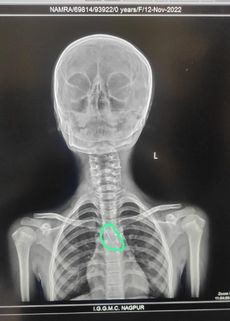

Nagpur News हिजाबला लावलेली टोकदार पीन चुकून गिळल्याने श्वासनलिकेत जाऊन अडकली. मेयो रुग्णालयातील डॉ. जीवन वेदी व त्यांच्या चमूने ही पीन काढून तिला जीवदान दिले.

नागपूर : हिजाबला लावण्यात येणारी टोकदार पीन एका सहावीतल्या मुलीने चुकीने गिळली. ती श्वासनलिकेत जाऊन फसली. मेयोचा कान, नाक व घसा (ईएनटी) विभागाचे प्रमुख डॉ. जीवन वेदी व सहकारी डॉक्टरांच्या चमूने विना शस्त्रक्रिया टोकदार पीन यशस्वीरित्या काढून मुलीचे प्राण वाचविले.

संगमनगर येथे राहणारी ११ वर्षीय शबाना (बदलेले नाव) शनिवारी शाळेत गेली. सुटीत आपला हिजाब नीट करण्याकरता तिने पीन काढून दातांमध्ये धरून ठेवली. परंतु आकस्मिकरित्या तिने ती पीन गीळली. तिला त्रास सुरू झाला. तिला घरी नेण्यात आले. आई-वडिलांनी तिला तातडीने मेयो रुग्णालयातील ईएनटी विभागाच्या ‘ओपीडी’त आणले. येथील डॉक्टरांनी तत्परता दाखवित ‘एक्स-रे’ काढला. गिळलेली पीन श्वासनलिकेत फसलेली दिसली. डॉक्टरांच्या चमूने तिला अॉ परेशन थिएटर मध्ये हलविले. विभाग प्रमुख व कॉकलीअर इंप्लांट सर्जन डॉ जीवन वेदी त्यांच्या अनुभव व कौशल्याने विना आॅपरेशनने ‘ब्रोन्कोस्कोपी’द्वारे श्वासनलिकेला कोणतीही इजा होऊ न देता यशस्वीरित्या बाहेर काढली. यात त्यांना डॉ विपीन ईखार, डॉ (मेजर) वैभव चंदनखेडे, निवासी डॉक्टर, तसेच बधिरीकरण तज्ञ डॉ वैशाली शेलगावकर व चमूचे सहकार्य मिळाले.

- टाचणीसारखी पीन असल्याने काढताना जोखीम

हिजाबला लावणारी पीन ही टाचणीसारखी होती. उपचारात आणखी उशीर झाला असता तर ती श्वासनलिकेत छिद्र पाडण्याची किंवा पुढे ती जाऊन रुतून बसण्याची शक्यता होती. शिवाय काढताना पीन सुटून छिद्र होण्याची भिती होती. परंतु अनुभव व कौशल्याच्या बळावर विना शस्त्रक्रिया श्वसननलिकेतून पीन काढणे शक्य झाले.